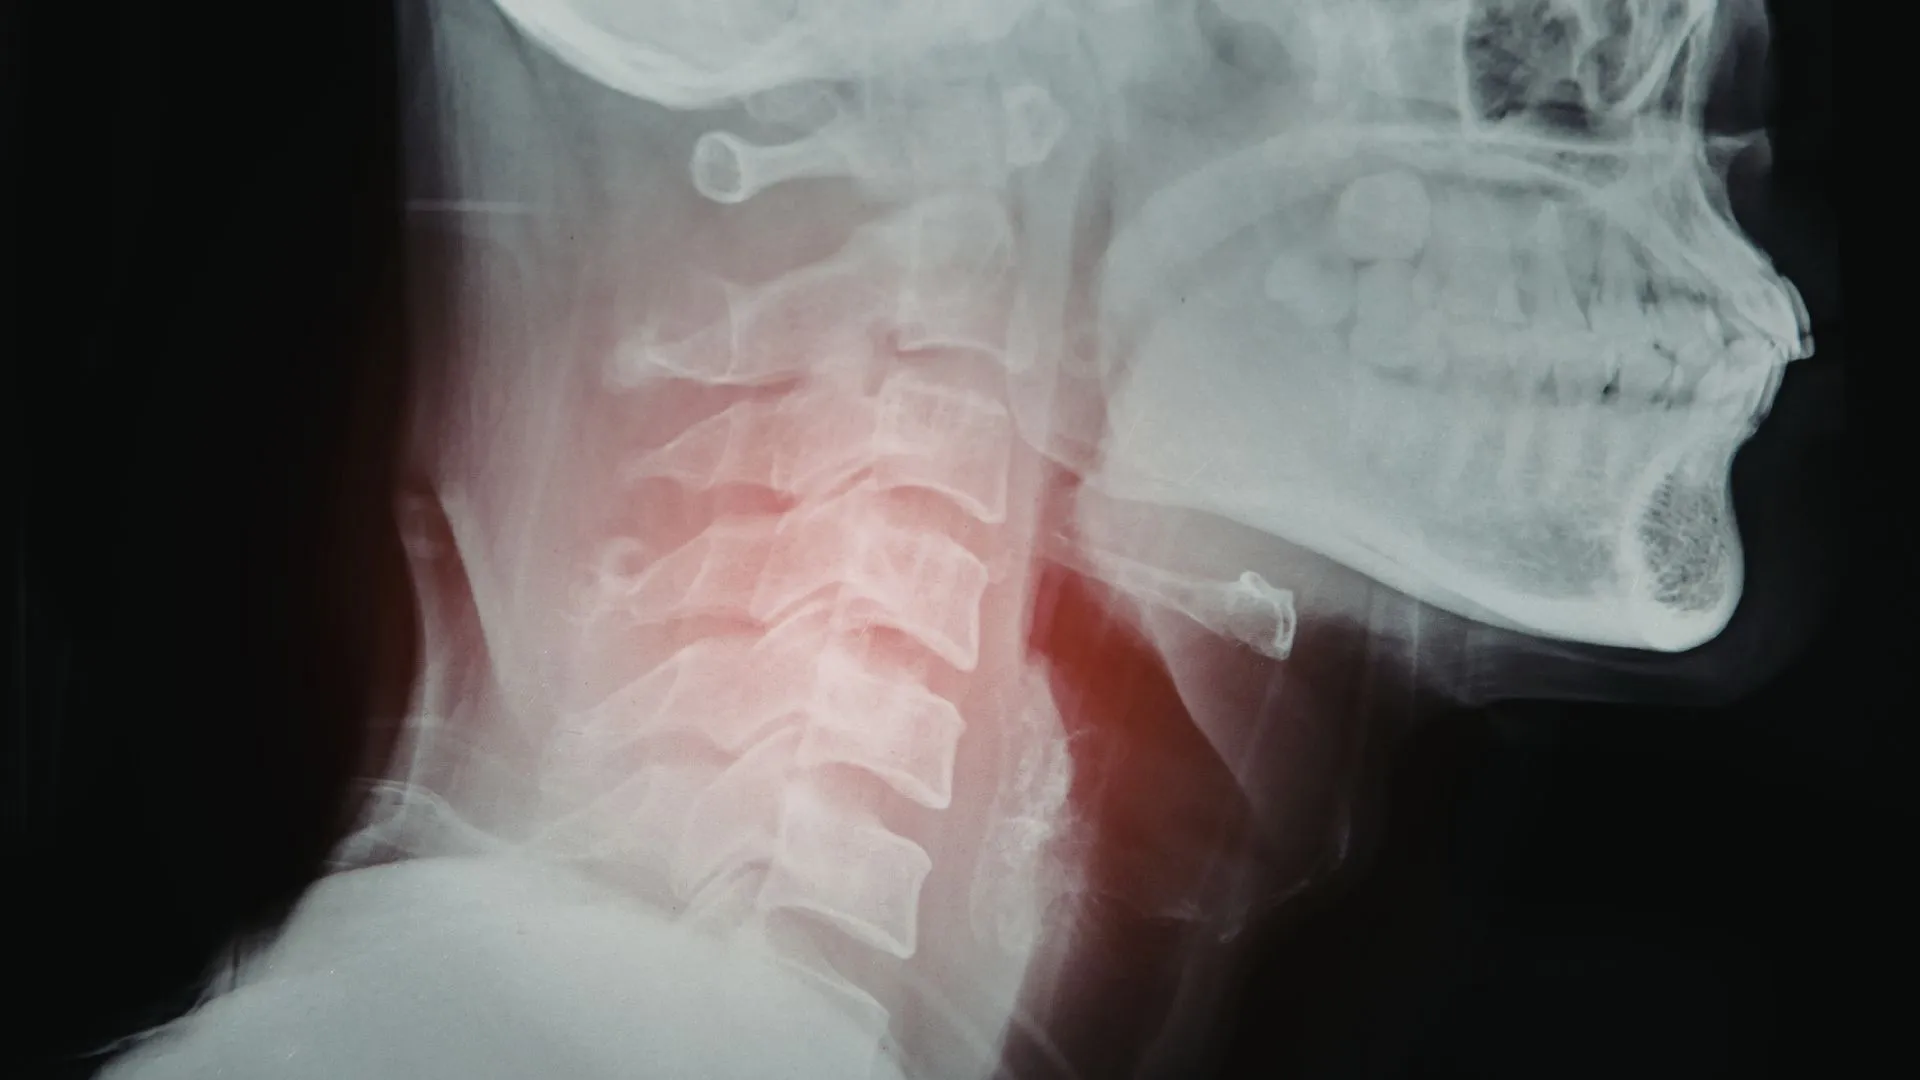

Cervical Spine and Its Components

The cervical spine includes seven vertebrae, labeled C1 to C7. These bones support your head and protect your spinal cord.

Each level serves a role. The C1 vertebra supports the skull and allows nodding. The C2 vertebra allows rotation. The lower cervical vertebrae provide stability and controlled movement.

Between each vertebra sits a disc. Discs absorb shock and allow smooth motion. Ligaments hold the structure together. Muscles guide movement and support posture. Nerves exit at each level and travel into your shoulders, arms, and hands.

A cervical nerve chart helps map how each nerve relates to specific areas of your body. This helps link symptoms such as pain, tingling, or weakness to a specific spinal level.

When this system loses proper movement or alignment, you feel pain, stiffness, or weakness.